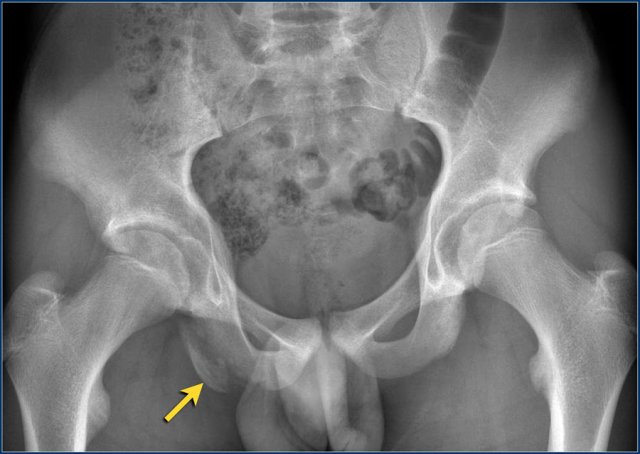

Slipped Capital Femoral Eiphysis

Slipped Capital Femoral Epiphysis (SCFE) or femoral epiphysiolysis is an idiopathic Salter-Harris type I fracture of the proximal femoral epiphysis.

It occurs more commonly in boys and in obese children. The typical age at presentation is between 12-15 years.

SCFE may occur bilaterally in up to one third of cases.

The epiphysis slips posteriorly, and to a lesser extent medially.

It is therefore best appreciated on the frog-leg lateral view.

SCFE is treated with surgical fixation to prevent further slippage.

Avascular necrosis of the femoral epiphysis is a potential complication.

Typical avulsion injury of the anterior inferior iliac spine at the insertion of the rectus femoris tendon.

Typical avulsion injury of the right ischial aphophysis.